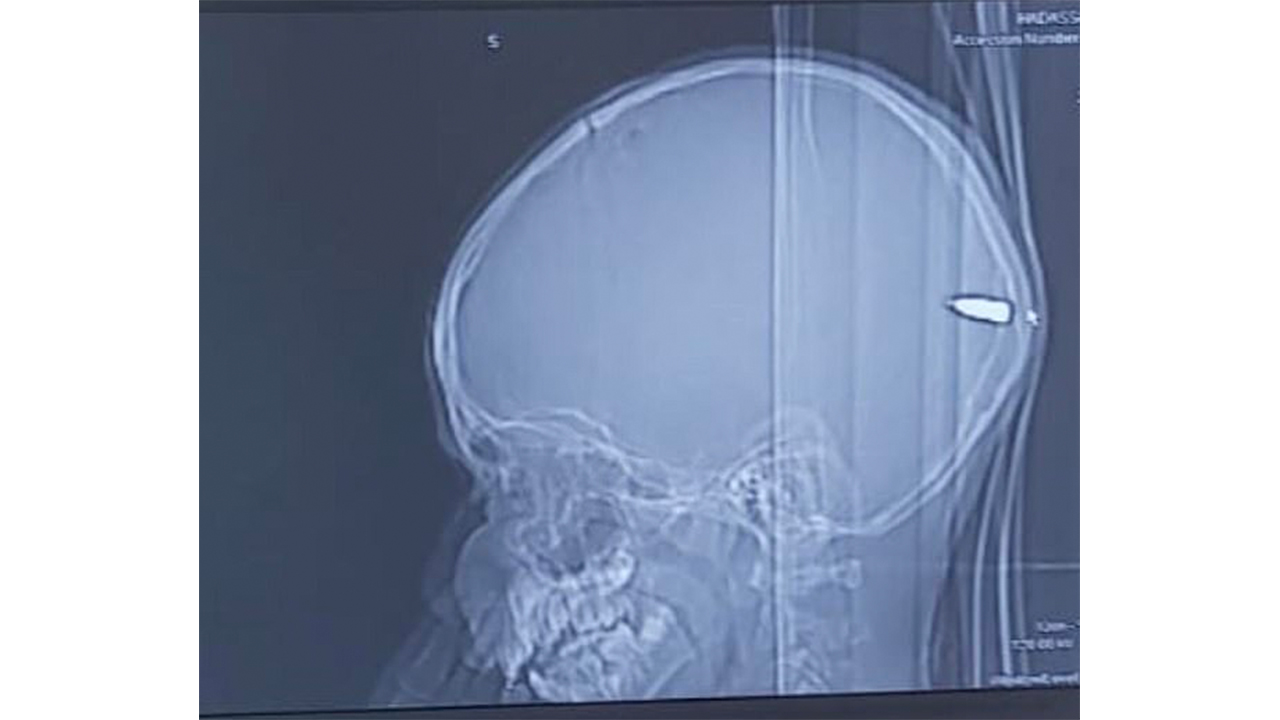

وأصيب الأطباء الذين أجروا الأشعة المقطعية بالذهول عند اكتشاف رصاصة مخزنة في دماغ الطفل.

قالوا إن الرصاصة دخلت جانب جمجمته قبل أن تمر عبر دماغه وتتوقف في مؤخرة رأسه.